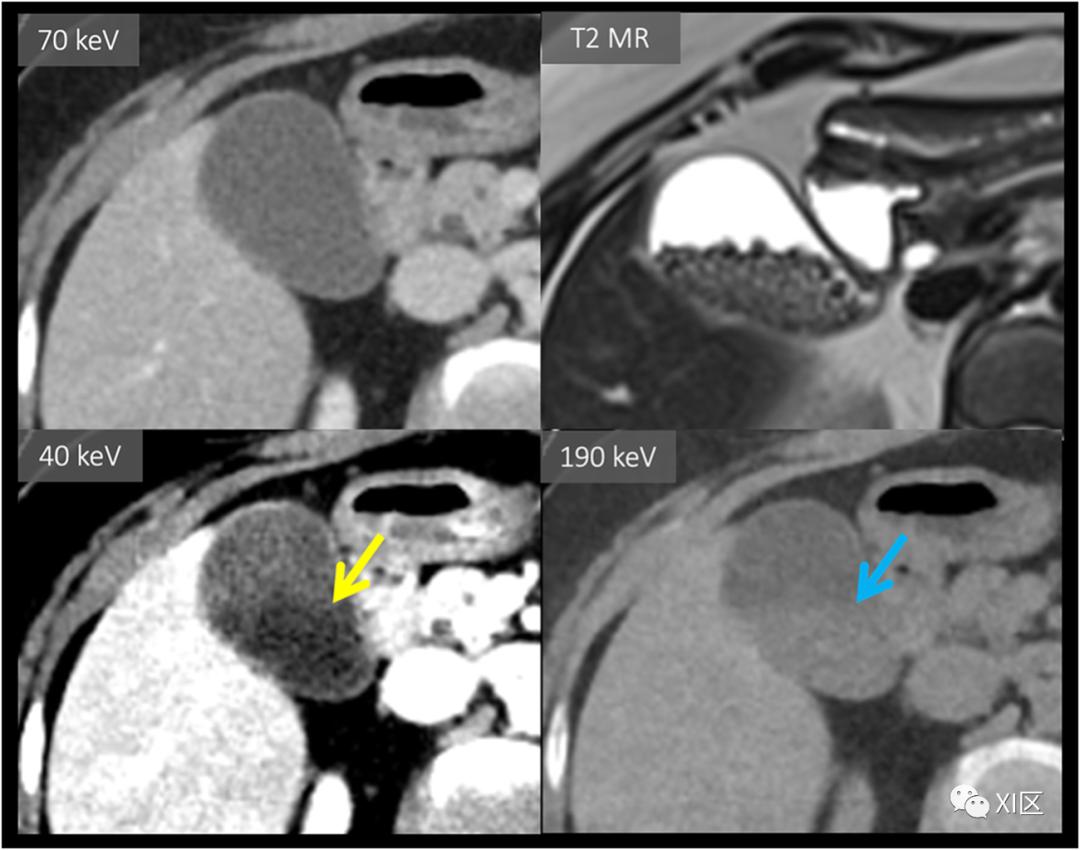

虚拟单能成像

在这些应用中,高能量和低能量数据的测量衰减通过基对的适当线性组合进行组合,以计算如果患者可以使用单一keV能量的纯单能X射线源照射,预期的图像外观。模拟的低keV虚拟单能(VME)图像强调了碘的x射线衰减,并可用于在碘增强的基础上更好地显示组织间的图像对比度。这种方法被广泛应用于优化胰腺肿块和低对比度肝脏病变的可视化,以及描述头颈部肿瘤对甲状腺软骨的侵犯。低keV图像也增加了血管增强,并已被用于挽救CTA检查的图像质量,或创造良好的CTA图像质量,以及对肾功能不良的患者减少对比剂负荷。高keV图像可用于去除碘的大部分增强,以模拟非对比增强图像。高keV图像也被用于DECT金属伪影减少,特别是矫形外科应用。它们在CTA中用于金属伪影的减少,但受到高keV下碘衰减同时丢失的挑战。根据我们的经验,金属伪影的减少通常可以通过制造商的各种基于投影域的金属伪影减少技术来更为可靠地完成。

肾损害评估与多囊肾

DECT碘选择性显像已被证明在根据病变内是否存在碘强化的基础上,有助于鉴别良性高密度囊肿和强化肾肿块。肾脏肿块评估通常包括多期肾脏肿块CT或MRI检查,包括平扫期、实质期和延迟期。由于扫描期相之间的错误配准限制了磁共振减影图像的应用,这些问题常常受到阻碍。然后,图像判读要求在手动放置的感兴趣区域中,在单独的、可能错误配准的扫描阶段对HU值(或MRI信号)进行比较。这对常染色体显性遗传性多囊肾病患者尤其具有挑战性,他们有更高的患肾细胞癌的风险,并且可能有比单纯液体衰减更高的多个病变。DECT可以简化多囊肾的评估,因为生成的碘含量本质上与VNC信息共同配准,如图7所示。这种方法已经被证明可以减少解释时间,并提高放射科医生对被评估的肾损伤中是否存在碘含量的信心。